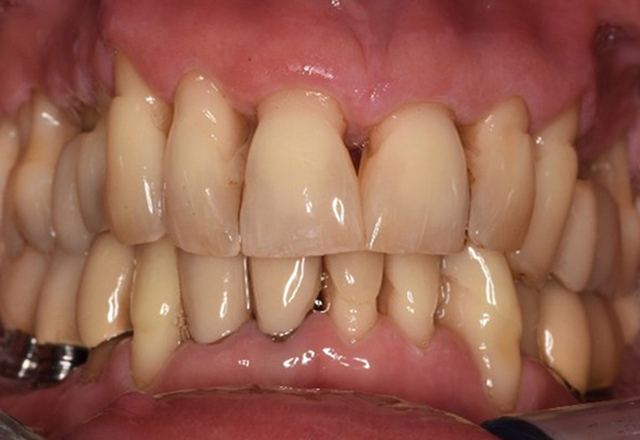

The healthy patient with pre-existing periodontal disease & peri-implantitis

Paciente sana con enfermedad periodontal previa

La paciente de 68 años no tiene enfermedades previas relevantes de la salud general ni toma medicación; sus hábitos alimentarios tampoco suponen un riesgo especial. La paciente tiene dos implantes (tercer cuadrante, desde hace cinco años) y una enfermedad previa periodontal (periodontitis en etapa IV, grado B) con pérdida dental. Actualmente las condiciones periodontales son estables, pero la periodontitis aumenta de manera determinante las complicaciones biológicas cuando se realizan implantes y puede ocasionar la pérdida de un implante (21). Para la sesión de profilaxis se hacen cuatro recomendaciones. más información